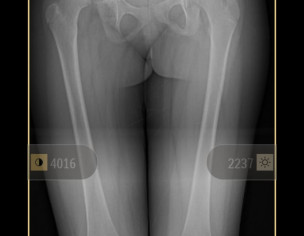

My daughter is diagnosed with hip dysplasia at age of 8.8 years. Doctor is saying for surgery immediately but we got another opinion and that surgeon is saying that there is no success rate of surgery right now. You have to wait once she grow up n then we will go for hip replacement. While the other doctor is saying that surgery is must. We need an opinion on it. Xrays are attached

she definitely need surgery to keep the head at level of socket. you should consult DR. CHIRAGH at GHURKI TRUST HOSPITAL, LAHORE. He is very experienced and expert for this disease.

it needs operation as soon as possible.

Surgery at present at 9yrs of age won't result good results. And re-dislocation may occur soon after surgery. Wait for maturity and then go for translational osteotony/replacement surgery.

Salam, She needs to get MRI of hip joint to measure angles related to hip dysplasia and clinical exam as well before deciding surgery. Thanks